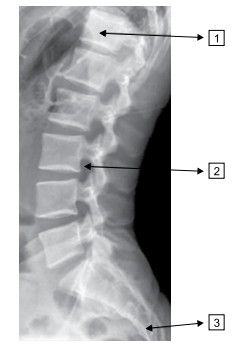

Quais regiões da coluna são assinaladas na imagem a seguir?

Provas